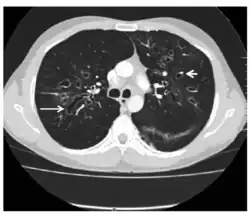

CT showing ‘signet ring’ (short, thick arrow) and ‘string of pearls’ (long, thin arrow) appearances, indicative of central bronchiectasis. Mucoid impaction and dilated bronchi are also seen. -